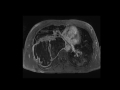

Malignant peripheral nerve sheath tumor in NF-1

MRI images in a patient with neurofibromatosis type I demonstrate a large, aggressive mass in the right hemithorax, compatible with malignant degeneration of a perihepheral nerve sheath tumor.